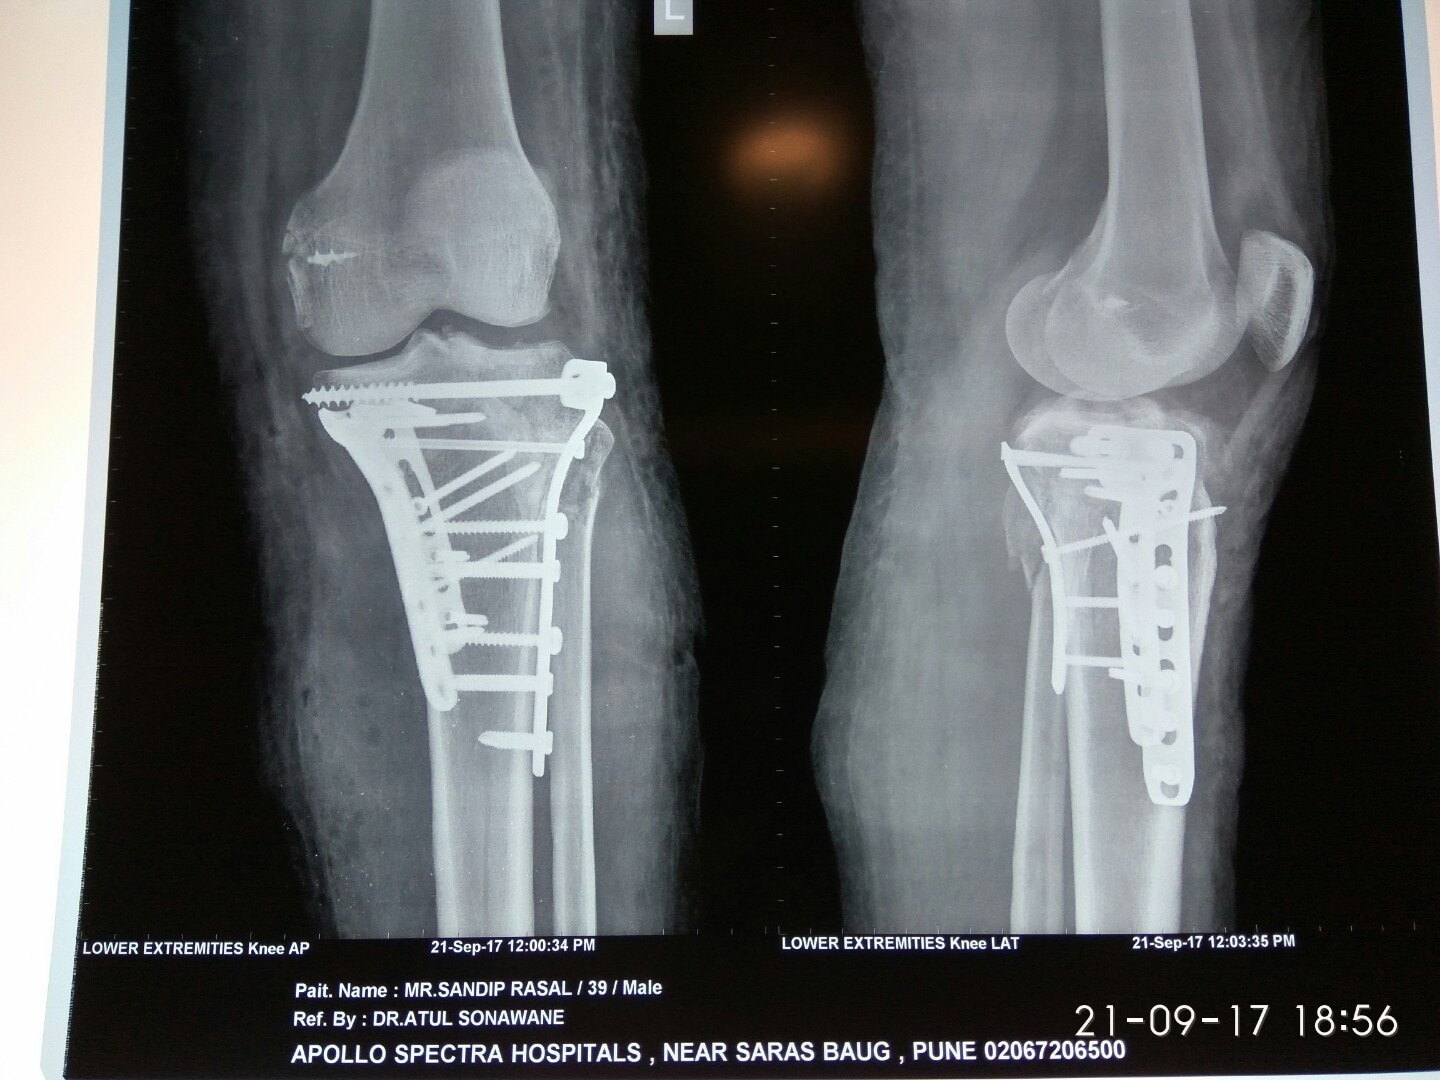

Dr. Sonawane Orthocare clinic is a centrally located Orthopedic Clinic In Pune city near Swargate at Hirabaug Business Centre, Hirabaug chowk, Tilak Road, Shukrawar peth and has easy accessibility from all parts of the city with multiple modes of travelling and enough parking spaces for patients’ own vehicles. Clinic is very modern and stylish and has air conditioned waiting area with comfortable sitting arrangement along with other amenities like TV, Wi-Fi, newspapers. There is hassle-free appointment and consultation system which is totally computerized. Patients get system generated appointment messages, reminders for follow-up dates and prescriptions through messages and emails. So its easy to keep track, keep and carry records and access it anywhere in the world. Clinic offers in-house digital X-ray, pathology tests and physiotherapy facilities at very reasonable rates. This makes the clinic a one stop destination for the patients they don’t need to go anywhere else for these facilities, saving lots of time and effort to get the treatment. We at Dr. Sonawane Orthocare clinic are committed for the best orthopedics care and proud to be one of the best orthopedics clinics in Pune.